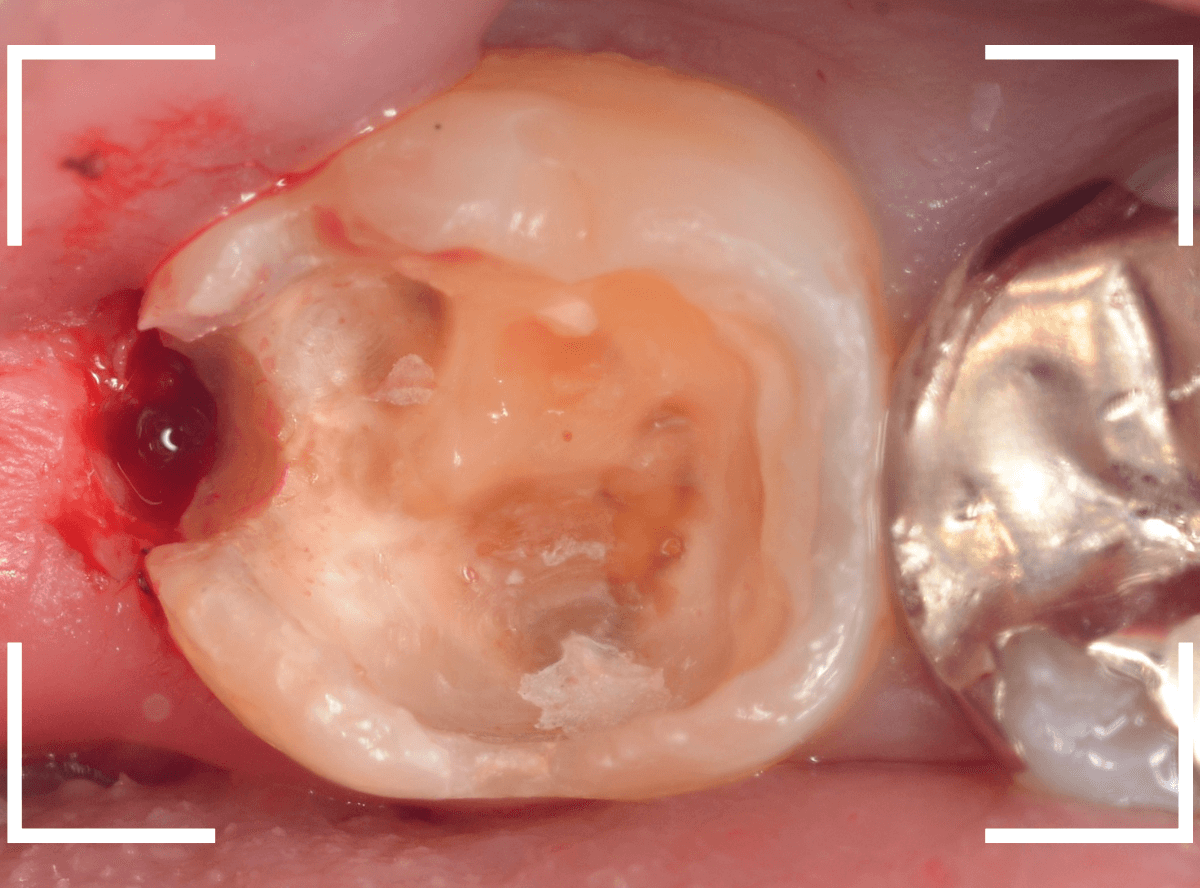

Case.12 下の一番奥の歯が、奥からひどい虫歯

「下の一番奥の歯が痛い」という訴えで来院された患者さんの例です。

一見では、特に問題ないように見えます。

レントゲン写真で確認します。

青いラインが歯の神経、赤いラインが虫歯です。

歯の奥の見えない部分から、大きな虫歯になっているのがわかります。

神経を除去しなければいけないかもしれないくらいの虫歯です。

治療を開始します。

歯の奥の部分を少し削ると、虫歯が出てきました。

慎重に虫歯を除去します。

歯肉ラインの下まで虫歯が進行しているため、虫歯の上に歯肉が広がっており、虫歯の見分けがつきづらい状況になっています。

虫歯を取り残さないように、余分な歯肉を除去します。

電気メスで、虫歯周囲の歯肉を除去後、全ての虫歯を除去しました。

虫歯は深かったですが、なんとか神経寸前のところで食い止められました。

神経を保護するお薬をつめて、セメントで蓋をしてしばらく経過観察します。

経過観察後、痛みがない事が確認できれば、つめものを作製します。